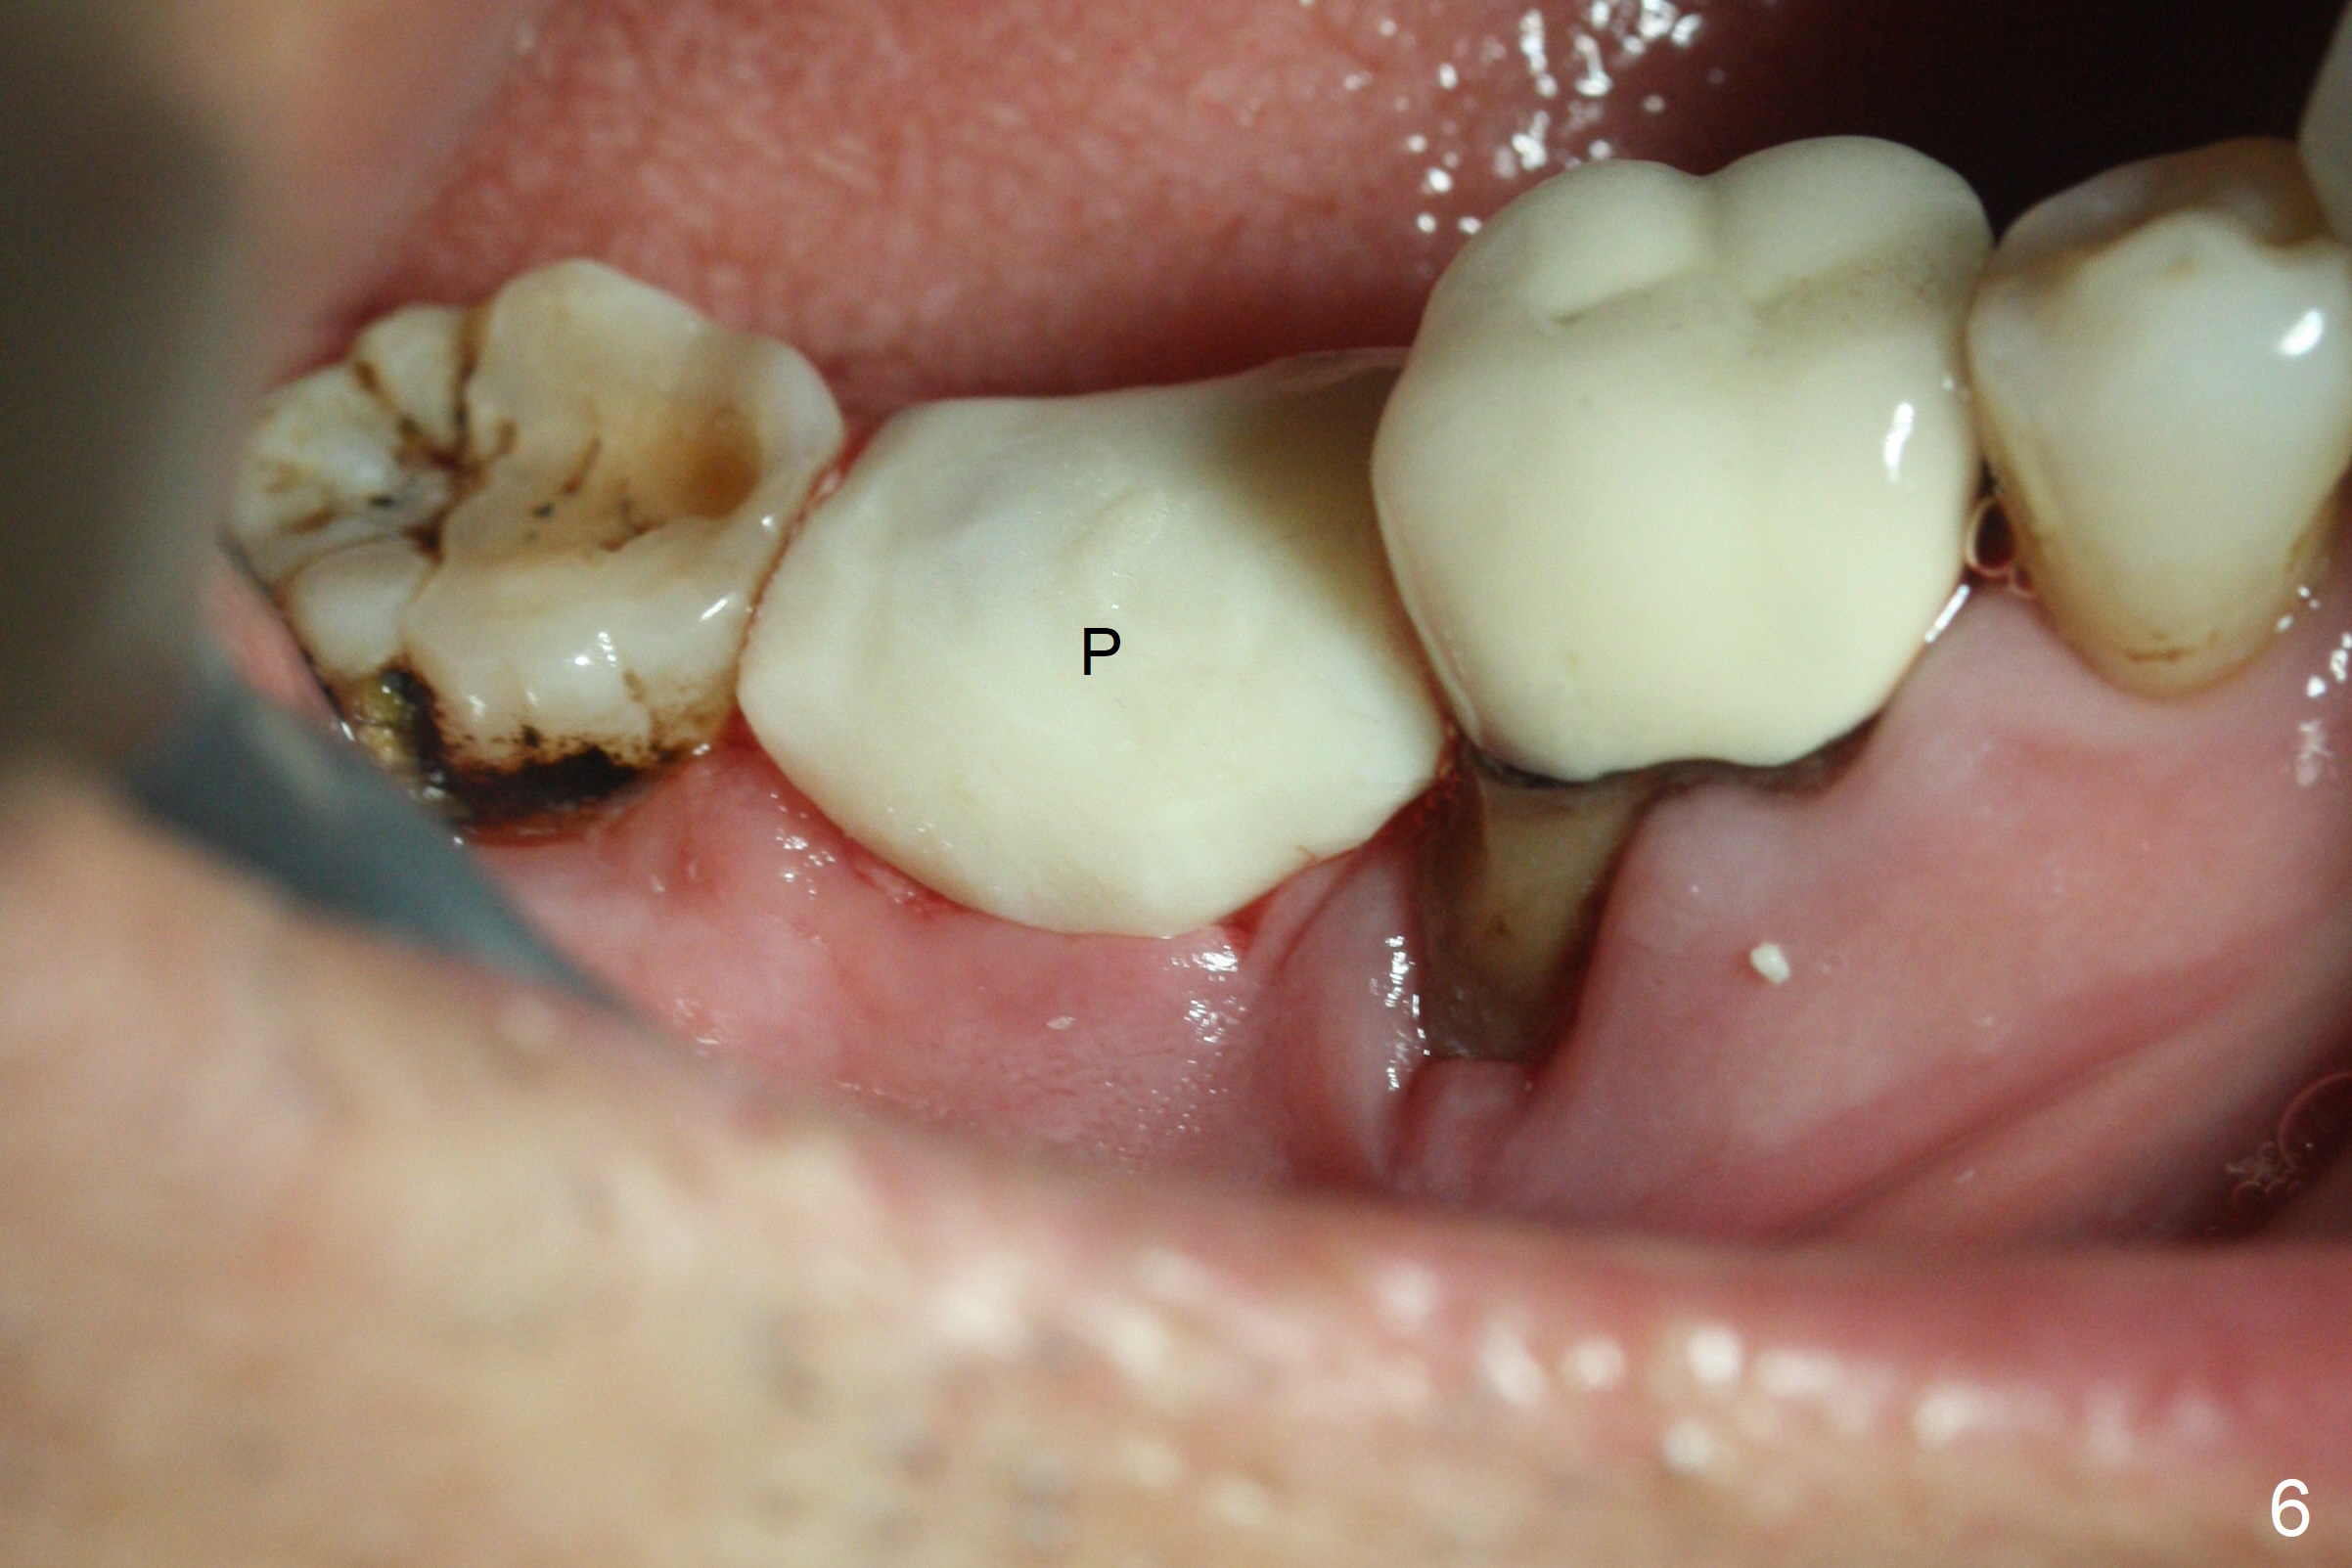

Although the tooth #30 has distobuccal root exposure (Fig.1 <), it is asymptomatic. In contrast the tooth #31 with the distoocclusal caries (*) is symptomatic. After use of 2 mm drill for 18 mm (lingual gingival margin), a calculated parallel pin is inserted (Fig.2 (D: 2 distal roots of the tooth #30)). It appears that a 11.5 mm long implant is appropriate for the site; a 5 mm cuff is expected. Following 4.8 mm drill, a 5.5x11.5 mm implant is placed initially (Fig.3) with an apical space (*) and clearance from the Inferior Alveolar Canal (red dashed line). The implant is placed deeper with placement of a 6.5x4(5) mm abutment and bone graft (*, Fig.4,5). After placement of collagen membrane over the graft, an immediate provisional is fabricated (Fig.6 P) with clearance from the opposing tooth (Fig.7 *). There is no bone loss 3.5 months postop (Fig.8). In fact the abutment has not been seated completely since its placement (Fig.4,5,8). The crown/abutment dislodges 3 years 3 months post cementation (Fig.9). The latter occurs for long incubation time because of opposing partial denture (Fig.10). After trimming proximal surfaces (Fig.11: arrowheads), the abutment remains incompletely seated (Fig.11) due to possible crestal bone interference (Fig.11 *). The smaller abutment by itself remains unseated (Fgi.12). One size small one is completely seated (Fig.13). Impression is taken. Two weeks later the abutment margin is supragingival. After screw torque at 20 Ncm, the crown is cemented with access hole. Excess cement is removed.